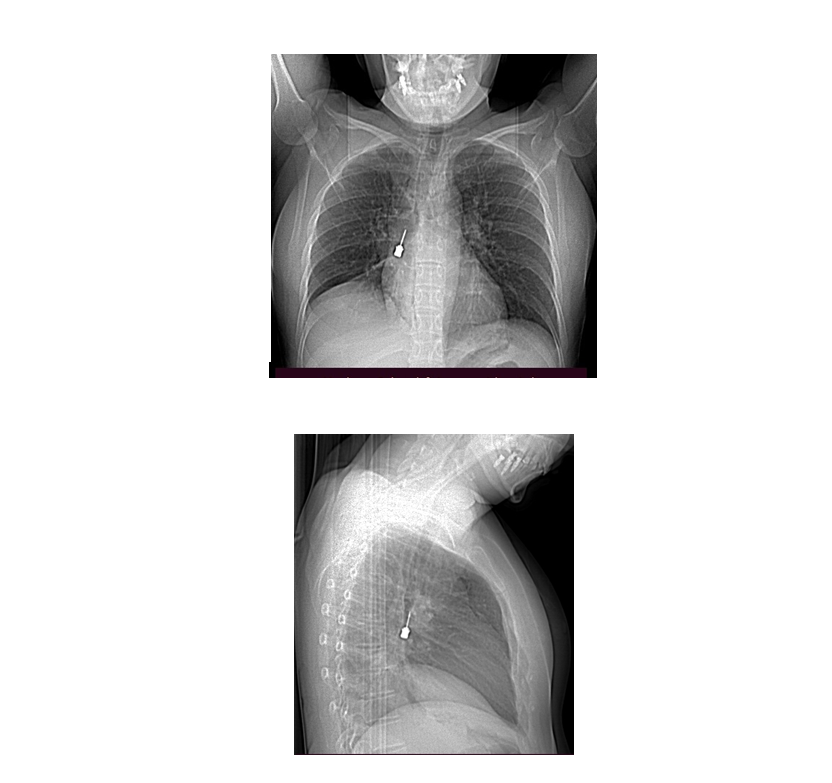

Il direttore dell’UOC di Chirurgia Toracica, dottor Baldassare Mondello, insieme al suo staff, ha effettuato con successo una delicatissima procedura endoscopica in urgenza, rimuovendo per via broncoscopica un cacciavite odontoiatrico accidentalmente inalato da una giovane donna.

La paziente si era presentata al Pronto Soccorso del GOM lamentando una tosse persistente e un forte dolore toracico, portando con sé una Tomografia Computerizzata che evidenziava la presenza di un corpo estraneo metallico pericolosamente incastrato nel bronco lobare inferiore del polmone destro, associato a un pneumomediastino, ovvero aria nello spazio tra i due polmoni.